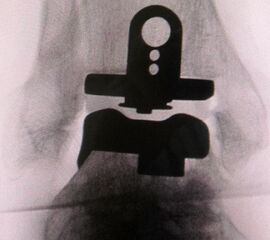

• Prothesenplanung anhand von Röntgenschablonen (Abb. 1 und 2).

5. Plazierung der Tibiakomponente in Varus- oder Valgusfehlstellung:

Die intraoperative Überprüfung der mechanischen Beinachse nach Festlegung der Resektionsebene ist empfehlenswert. Eine asymmetrische Resektion ist bei präoperativ pathologischem distalen Gelenkwinkel erforderlich.